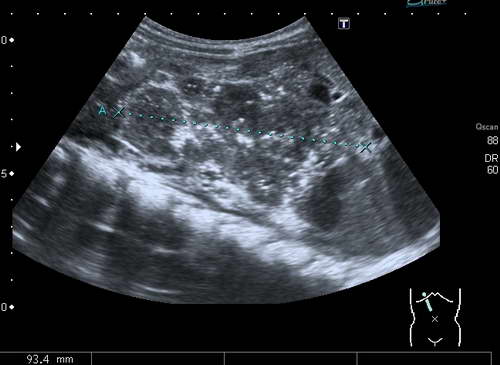

- Ультразвуковое исследование (УЗИ) брюшной полости – помогает обнаружить жидкость в полости, изменения в стенках кишечника и оценить его функциональность. Этот метод также позволяет оценить состояние мезентериальных сосудов и выявить наличие тромба или эмбола.

- Допплерография – используется для определения степени нарушений кровотока.